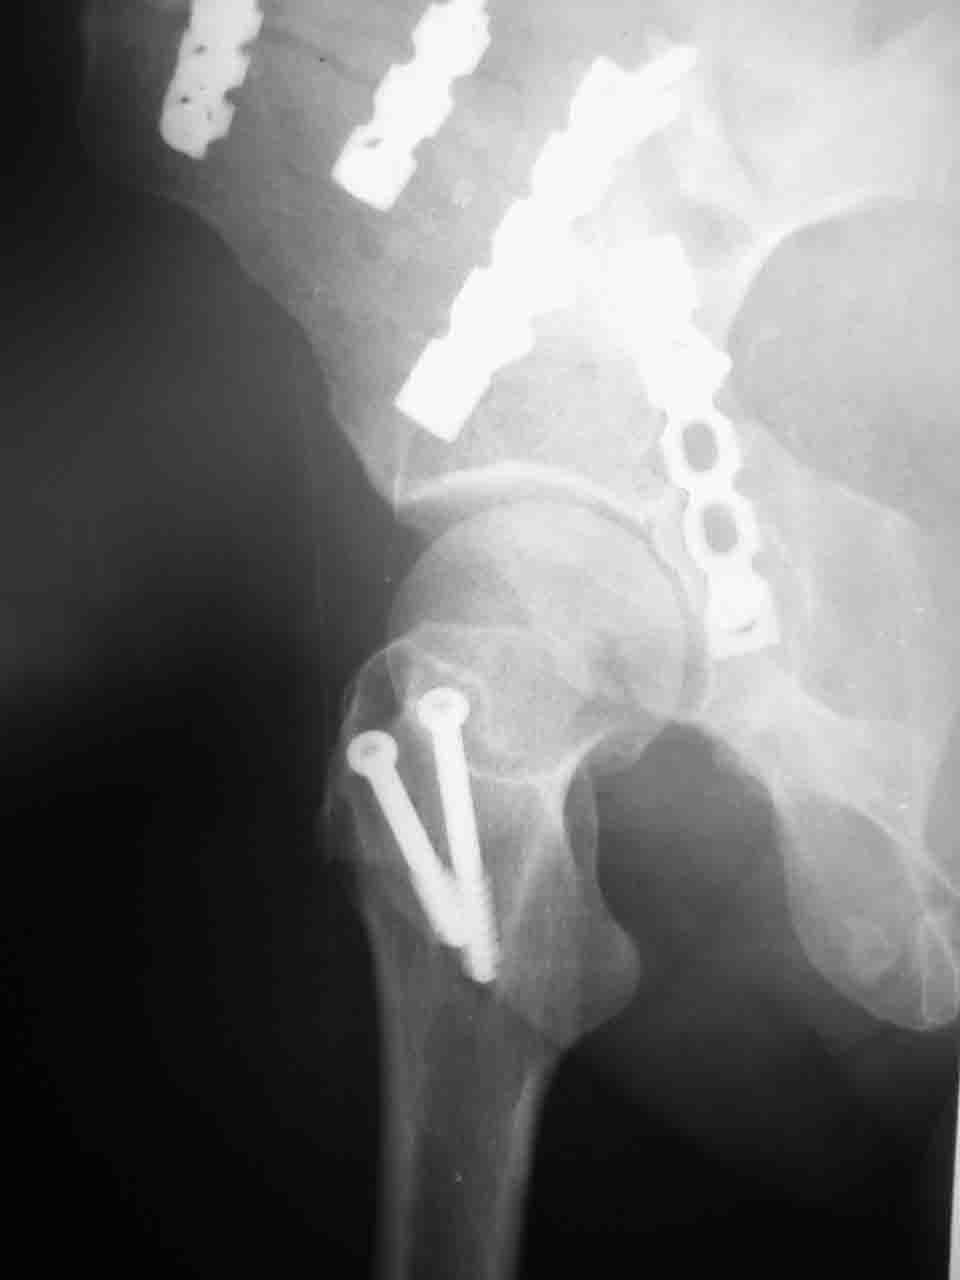

Сложностью, ассоциативностью характера перелома, я бы с радостью воспользовался мининвазивной перкутанной фиксацией винтами, но боюсь, что результат был бы ещё хуже, техникой непрямой репозиции перелома не владею, поэтому пытаясь получить анатомичную впадину приходится широко открывать, по крайней мере пока, а дальше буду пытаться уменьшать пространство...

Илеофеморальный доступ не совсем передний и сравнительно с илеоингвинальным, и Кохера-Лангенбека открывает весь наружный таз кроме самых передних отделов лонных костей, фиксацию которых я не ставил в задачу. Обширность диссекции, большая длительность операции и более высокий риск гетерооссификации - отрицательные моменты в обмен на возможность легче ориентироваться.

Вопрос доступа к вертлужной впадине при остеосинтезе задача не простая. Конечно, у Летурнеля и Тайла всё давно описано, нам остается только брать на вооружение. Но сами понимаете, что не бывает двух одинаковых ситуаций, поэтому в каждом случае вопрос решается сугубо индивидуально. Наша главная цель - восстановить анатомию с нанесением минимальной дополнительной травмы тазобедреннному суставу, думаю с этим никто не поспорит. Расширенный илиофеморальный доступ уж слишком травматичен (как сказал один коллега "таз лежит отдельно, больной отдельно").Стоит ли делать из пациента анатомический препарат для того чтобы легче ориентироваться. Да и нужно ли собирать всю "мозаику"? Мы применяли при таких операциях своеобразную операционную хитрость - сначала устраняли грубое смещение крыла под гребнем с фиксацией так называемой "плавающей" пластиной (временно фиксированной на двух винтах)- доступ или продлевали боковой, или делали небольшой дополнительный разрез над гребнем. Это позволяло устранить грубое смещение и захождение отломков тела повздошной кости, что значительно облегчало репозицию и остеосинтез впадины над сводом. Основное внимание конечно же уделяли нагружаемому задне-верхнему отделу. Сообщите ваш адрес, пришлю схемы и рентгенограммы.